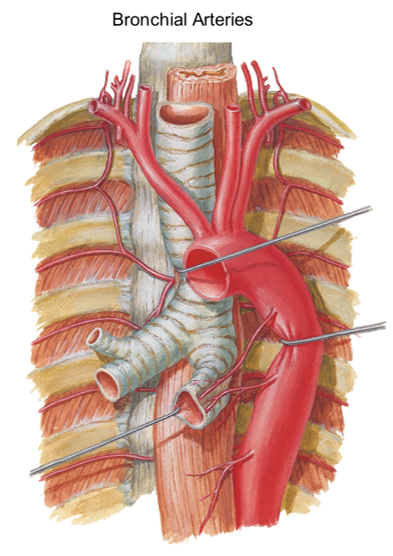

the bronchial arteries come from where? what will you commonly see with these?

from the aorta

you will see them coming from variable pathways from the aorta

in this person, what bronchial arteries can you point out?

you can point out the right bronchial artery and then on the other side, the left superior bronchial artery and the left inferior bronchial artery both going to the same bronchi tube on bottom

Bronchial veins:

- Right bronchial vein drains into the _____________?

- Left bronchial vein drains into the _______________?

azygos vein

accessory azygos vein

in picture, you can see the azygos vein on the left and the small vessel (right bronchial vein) draining into the azygos

on the other side you see the small left bronchial vein draining into the accessory hemi-azygos